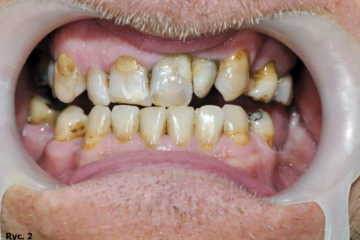

Pacjent B.J., lat 45, zgłosił się do gabinetu w celu poprawy estetyki i uzupełnienia braków zębowych. W badaniu zewnątrzustnym zaobserwowano wysunięcie bródki, wygładzenie bruzdy bródkowo wargowej, pacjent miał charakterystyczne wzmożone napięcie warg i kłopoty z wymową niektórych głosek. W badaniu wewnątrzustnym stwierdzono odwrotne zachodzenie zębów siecznych, zęby ustawione w III klasie Angle’a. Wynik dodatni testu czynnościowego bez poprawy rysów twarzy pozwolił postawić rozpoznanie: przodozgryz całkowity (ryc. 1, 2, 3).